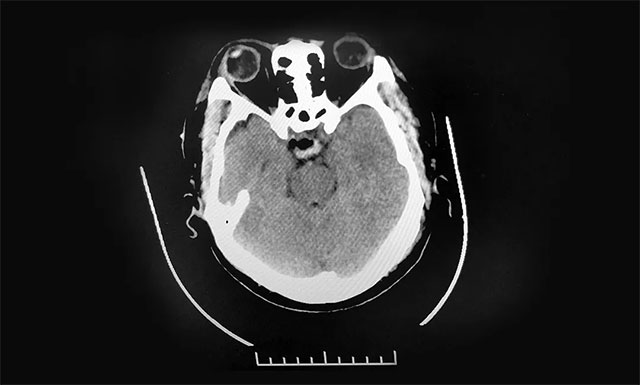

术后,患者头痛、视物重影症状已消失,视力明显改善,目前正在康复中。

▲ 术后影像显示肿瘤被切除